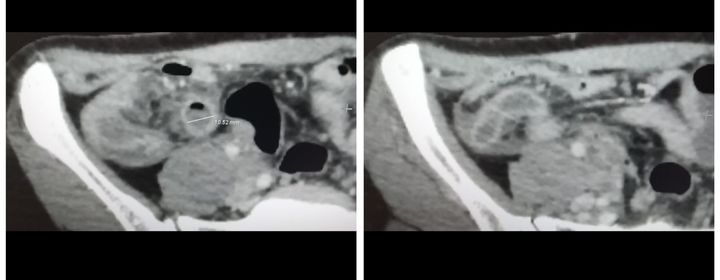

Acute appendicitis

37 years old woman presented to the emergency department with abdominal pain and vomiting. Physical examination revealed McBurney Point Tenderness and Rovsing sign. BT in appendix size 10.5 mm and periapendicular fluid